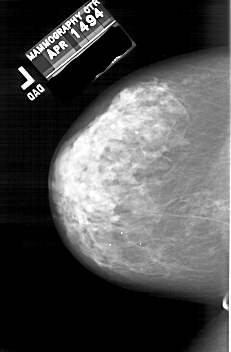

A_2000_1.LEFT_CC

LEFT_CC LINES 5971 PIXELS_PER_LINE 3916 BITS_PER_PIXEL 12 RESOLUTION 43.5 NON_OVERLAY